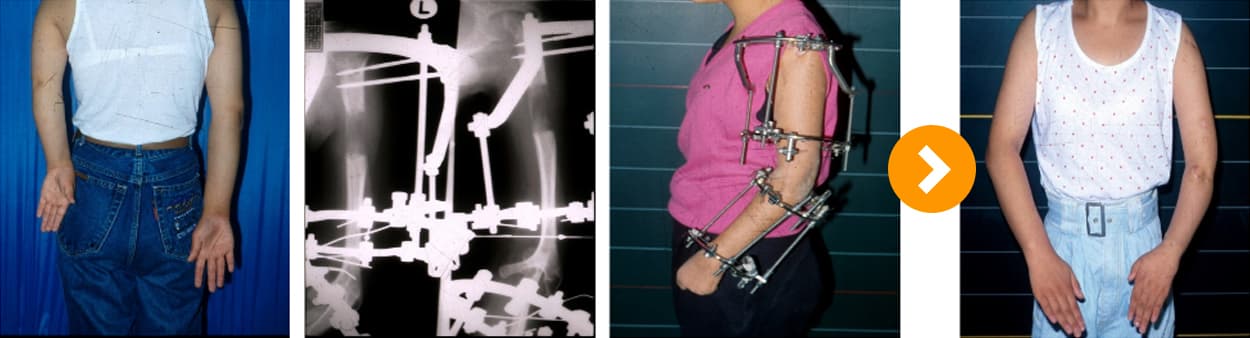

족부 기형 일리자로프 교정술